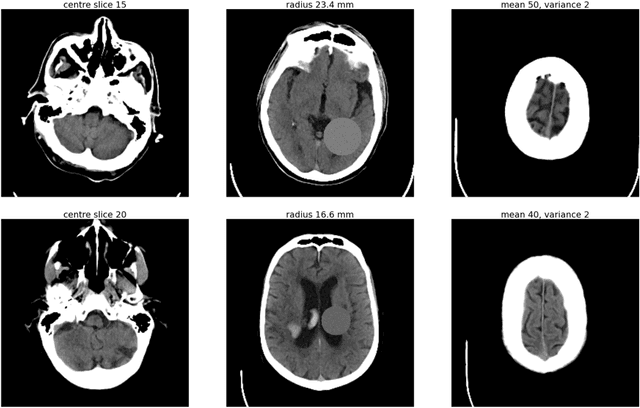

Abstract:As interest in applying machine learning techniques for medical images continues to grow at a rapid pace, models are starting to be developed and deployed for clinical applications. In the clinical AI model development lifecycle (described by Lu et al. [1]), a crucial phase for machine learning scientists and clinicians is the proper design and collection of the data cohort. The ability to recognize various forms of biases and distribution shifts in the dataset is critical at this step. While it remains difficult to account for all potential sources of bias, techniques can be developed to identify specific types of bias in order to mitigate their impact. In this work we analyze how the distribution of scanner manufacturers in a dataset can contribute to the overall bias of deep learning models. We evaluate convolutional neural networks (CNN) for both classification and segmentation tasks, specifically two state-of-the-art models: ResNet [2] for classification and U-Net [3] for segmentation. We demonstrate that CNNs can learn to distinguish the imaging scanner manufacturer and that this bias can substantially impact model performance for both classification and segmentation tasks. By creating an original synthesis dataset of brain data mimicking the presence of more or less subtle lesions we also show that this bias is related to the difficulty of the task. Recognition of such bias is critical to develop robust, generalizable models that will be crucial for clinical applications in real-world data distributions.